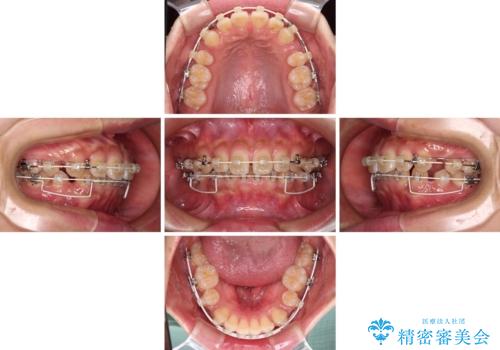

くちばしのような前歯 抜歯矯正で口を閉じやすく

- 審美装置

- 前歯の突出感を気にして来院された患者様です。

咬合力が非常に強く、咬合力で前歯が前方に押し広げられており、上下唇に閉じにくさが認められました。

上下左右の第一小臼歯4本を抜歯し、ワイヤー装置にて矯正治療を行うこととしました。